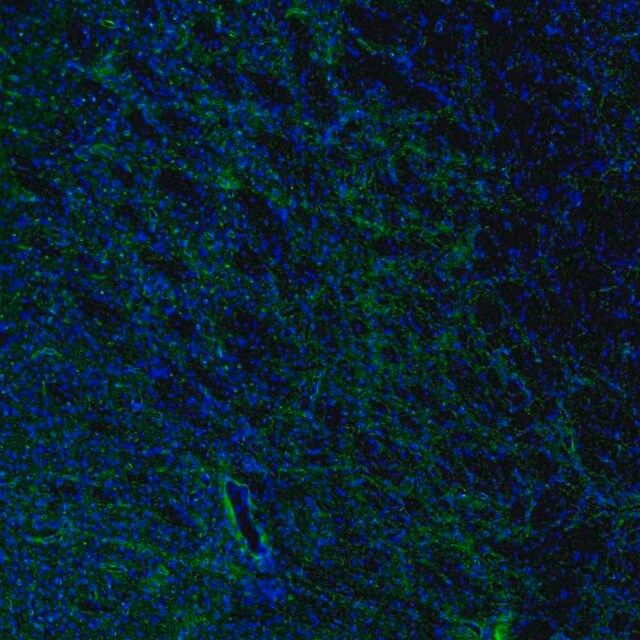

水通道蛋白 4 (aquaporin 4,AQP4) 是一种内源性蛋白,属于水通道蛋白家族,由 13 个成员组成。该基因位于人类 18 号染色体 q11-q12,有 4 个外显子和 3 个内含子。编码的蛋白有 5 个环,由 6 个跨膜结构域干预。环 A、C 和 E 面向浆外区,环 B 和 D 存在于胞浆区。在肺、胃和肾等外周器官中表达。是中枢神经系统表达的主要水通道。它由星形胶质细胞表达,并优先定位于星形胶质细胞的终足突起。它以两种可变剪接形式存在— 长的称为 M1,短的称为 M23。

人类蛋白质图谱项目可细分为三个方面的工作:人类组织图谱、癌症图谱和人类细胞图谱。支持 Tissue and Cancer Atlas 项目而产生的抗体,已经通过免疫组化针对数百个正常和疾病组织进行了测试,通过 Human Cell Atlas 项目最近的努力,很多已经通过免疫荧光法进行了表征,不仅在组织级别,现在也在亚细胞级别绘制了人类蛋白质组图谱。通过点击图像库链接,可以在 Human Protein Atlas (HPA) 位点上查看这些图像和这个庞大数据集的集合。要查看这些协议 和其他有关 Prestige 抗体和 HPA 的有用信息,请访问sigma.com/prestige。

水通道蛋白 4 (aquaporin 4,AQP4) 是脑内主要的水转运体,被认为是维持脑内水分稳态的重要物质。因此,AQP4 可能在脑水肿的发病机制中起重要角色。研究显示,这种转运体在脑缺血中过度表达。因此,它可能有潜力成为缺血性脑水肿的治疗靶点。该基因多态性与脑损伤反应和脑外伤患者的临床预后相关。AQP4 的短亚型 (M23) 有利于颗粒正交排列 (orthogonal array of particles,OAP) 的形成,OAP 的大小由短 (M23):长 (M1) 亚型的比例决定。已知这些 OAP 与视神经脊髓炎 (NMO) 中产生的致病性自身抗体相互作用。因此,对该蛋白的进一步研究可能为 NMO 的发病机制和治疗提供见解。